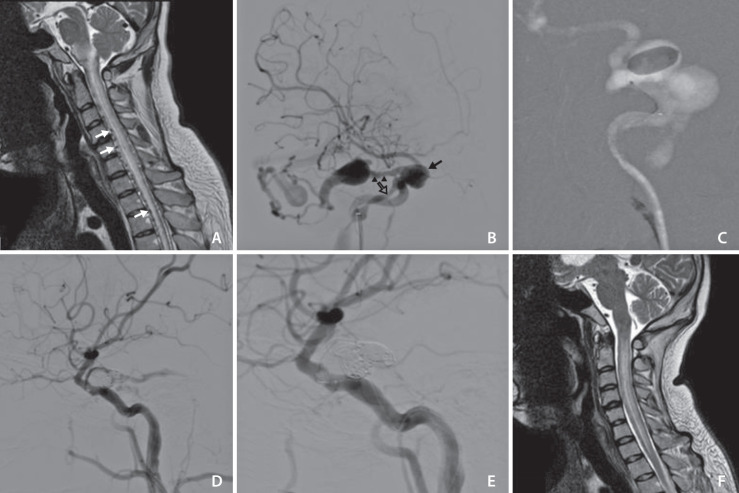

一名 24 岁的男性因进行性颈椎感觉减退、四肢瘫痪、呼吸困难和颅面骨折病史入院。脊髓磁共振成像(MRI)显示,脑干水肿延伸至胸椎,并伴有多个突出的髓周血管结构。脑数字抽取血管造影显示出巴罗A型颈动脉海绵瘘。使用 1 个可拆卸球囊和 6 个线圈,在保留颈内动脉血流的情况下实现了全闭塞。术后,患者呼吸功能立即恢复,四肢力量逐渐改善,右侧外展神经麻痹。一个月的颈椎磁共振随访显示脊髓水肿和髓周静脉恢复良好。

A 24-year-old male was admitted with progressive cervical hypesthesia, tetraparesis, dyspnea, and a history of craniofacial fracture. Spinal magnetic resonance imaging (MRI) showed brainstem edema extending to the thoracic spine with multiple prominent perimedullary vascular structures. Cerebral digital-substraction angiography revealed Barrow type A carotid-cavernous fistula. Total occlusion with preservation of internal carotid artery flow was achieved using 1 detachable balloon and 6 coils. Postoperatively, immediate respiratory recovery, gradual extremities strength improvement, and right abducens nerve palsy were found. One month follow-up cervical MRI showed good recovery of spinal cord edema and perimedullary veins.